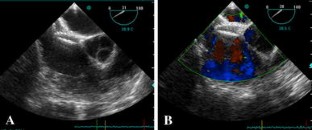

Fig. 1